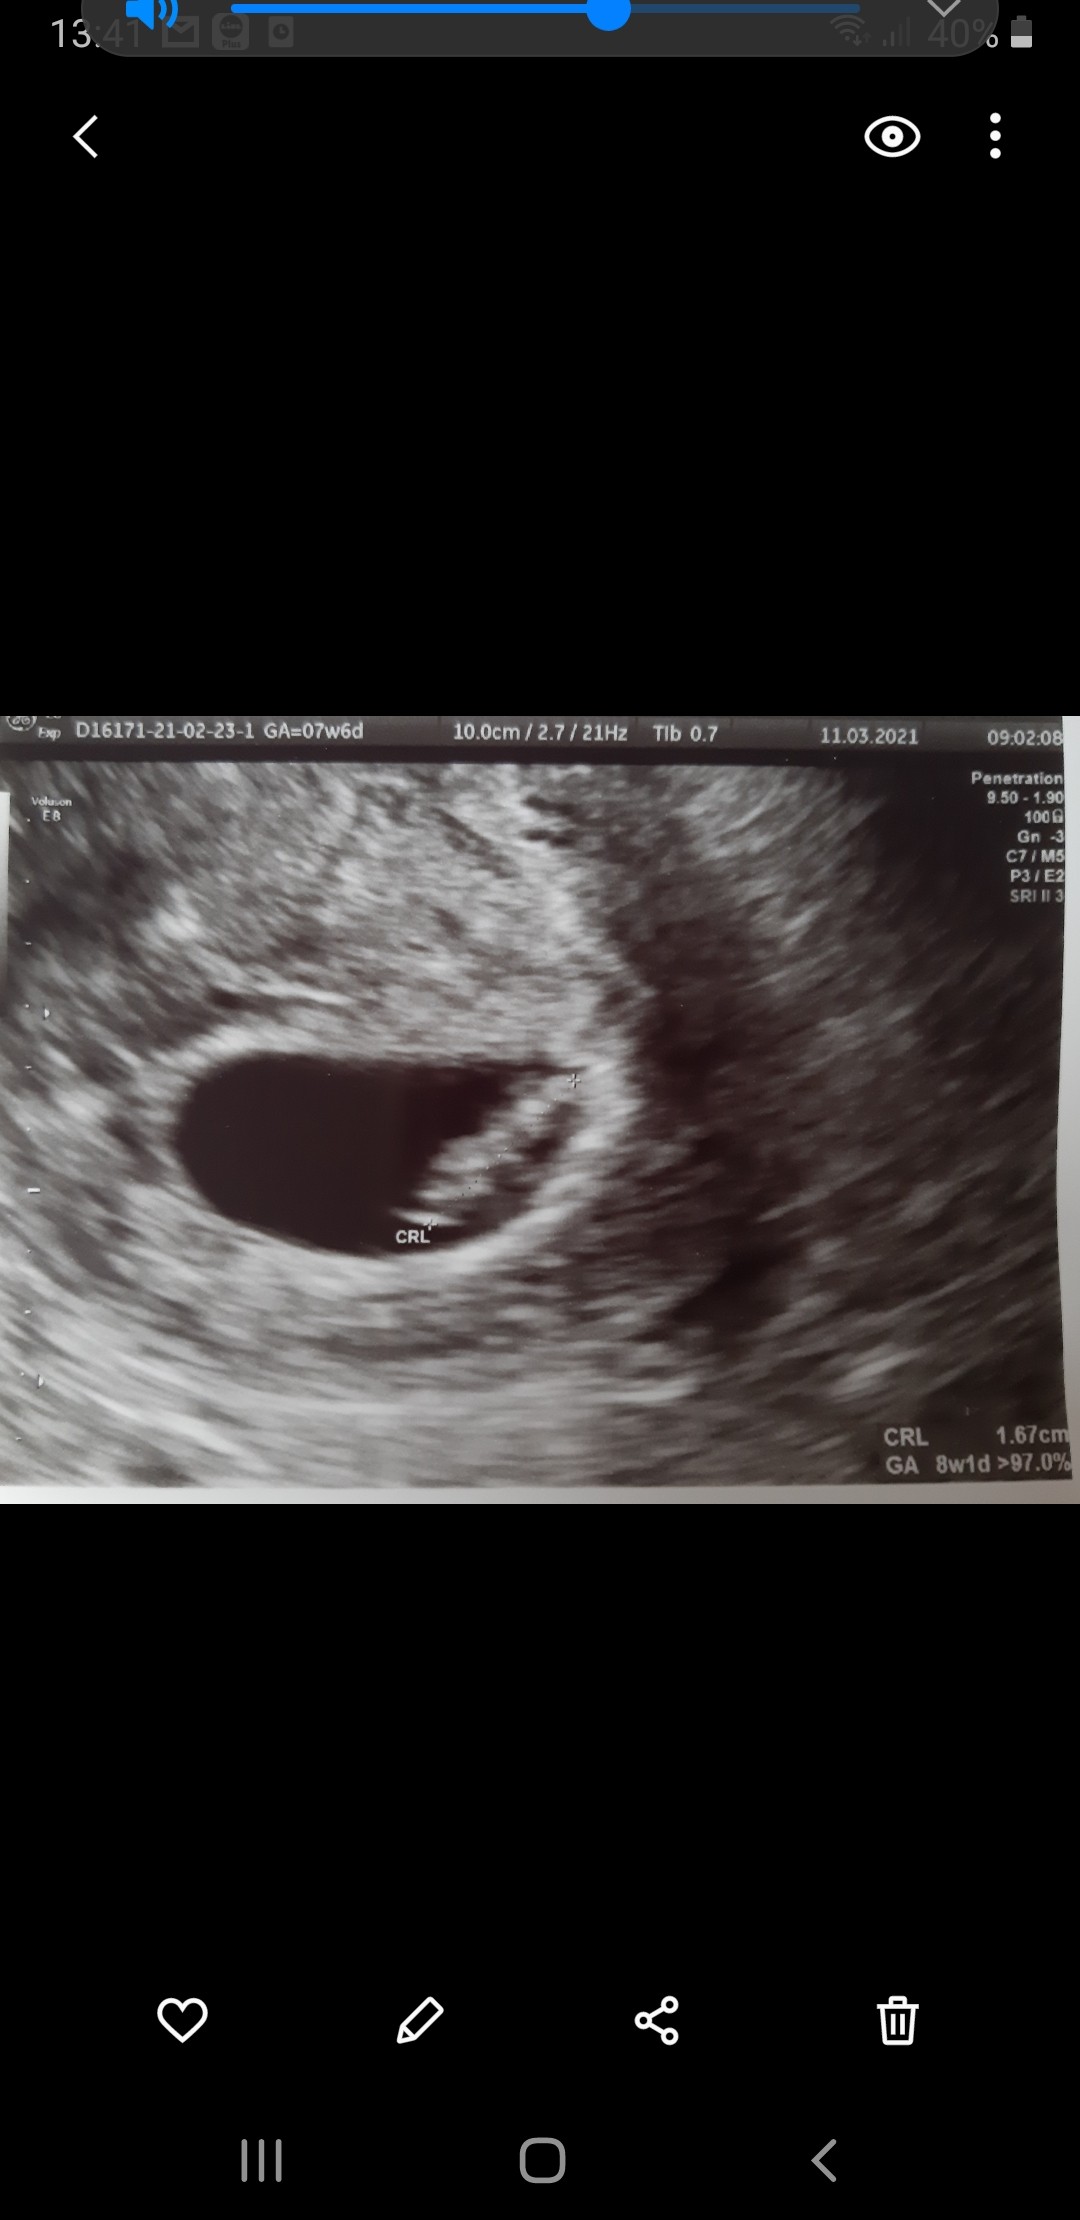

Hej ja tez po wizycie 😃

Bobas ma 3,93 cm 10+6 dziś

Za 1,5 tyg badania prenatalne,mam nadzieje ze wszystko będzie w jak najlepszym porządku 💕

18824493-D75E-4D7F-B0D0-D56FDE15D74F.jpeg